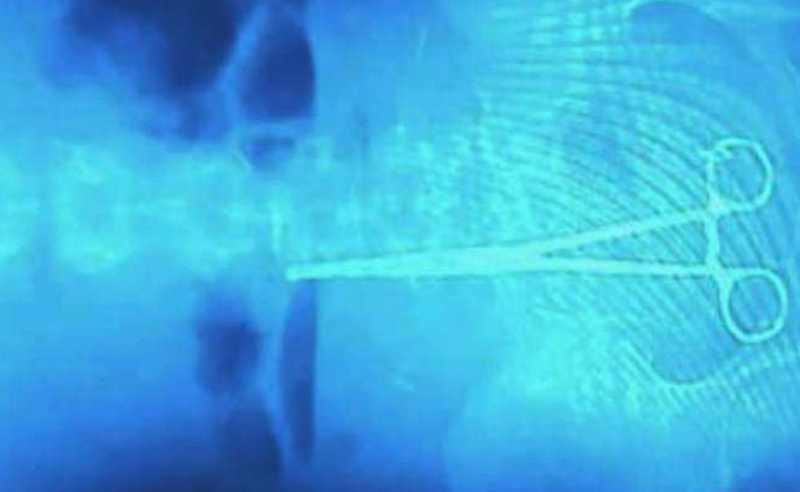

მარდალეიშვილი კლინიკა - მოხდა უცხო სხეულის ჩატოვება მუცლის ღრუში, 9 საათი მიმდინარეობდა ოპერაცია, მედპერსონალიც დაღლილი იყო